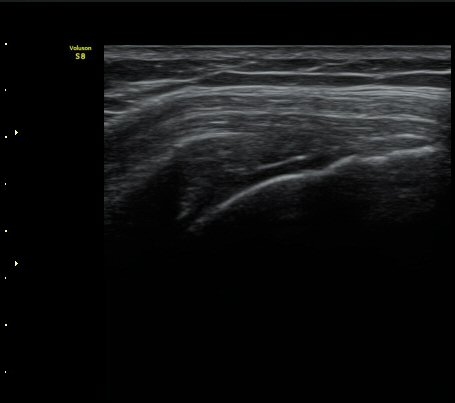

¾î±ú ±Ø»ó°Ç ÃÊÀ½ÆÄ°Ë»ó ±Ø»ó°Ç ºÎÂøºÎ°¡ °üÂûµÇÁö ¾Ê°í ±ÙÀ§ºÎ·Î ´ç°ÜÁ® ÀÖ´Ù(±×¸² 1, 2).

±Ø»ó°Ç Ⱦ´Ü¸é°Ë»ç»ó »ó¿Ï°ñµÎ¸¦ µ¤°í ÀÖ¾î¾ßÇÒ ±Ø»ó°ÇÀÌ º¸ÀÌÁö ¾Ê°í Á¡¾×³¶ÀÌ ÆíÆòÇϰÔ

³»·Á ¾É¾Æ º¸ÀδÙ(±×¸² 3).